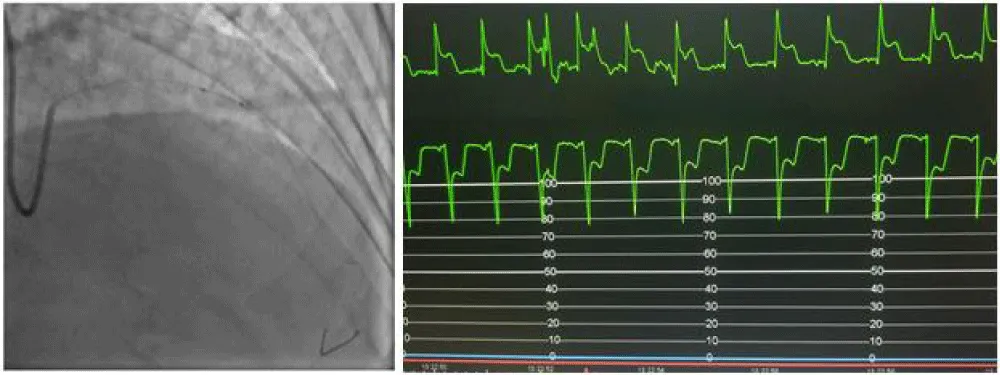

We gradually removed this emergency assembly that allowed us to release and retrieve the trapped balloon (Figure 5). The control injection revealed a thrombotic occlusion of the LAD treated by thrombectomy and anti-GPIIbIIIa followed by a DES 2.75% 28 placement that allows a TIMI III flow in the LAD at the cost of losing the small diagonal artery that we could not recross (Figure 6).

Figure 6: Management of the thrombotic occlusion of the LAD and result (A: Thrombectomy and balloon. B: result. C: ST regression. D: Stenting DES 2.75x28. E: Final result. F: Diagonal before PCI).

The patient remained stable after the procedure with normalization of his ECG and LVEF at 58% and was discharged 48 hours later.